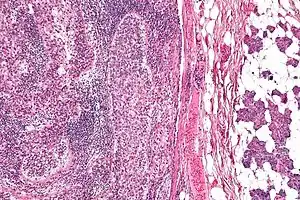

| Micrograph of a sebaceous carcinoma (left of image) metastatic to the parotid gland (right of image). H&E stain. | |